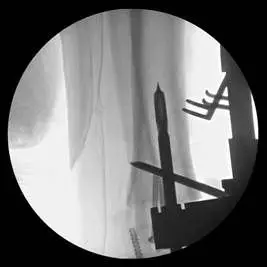

This is a pic of the implant getting mapped out for placement in the distal tibia

This is the guide for the tibia component of the implant

These are pics of the implant being placed in the ankle joint